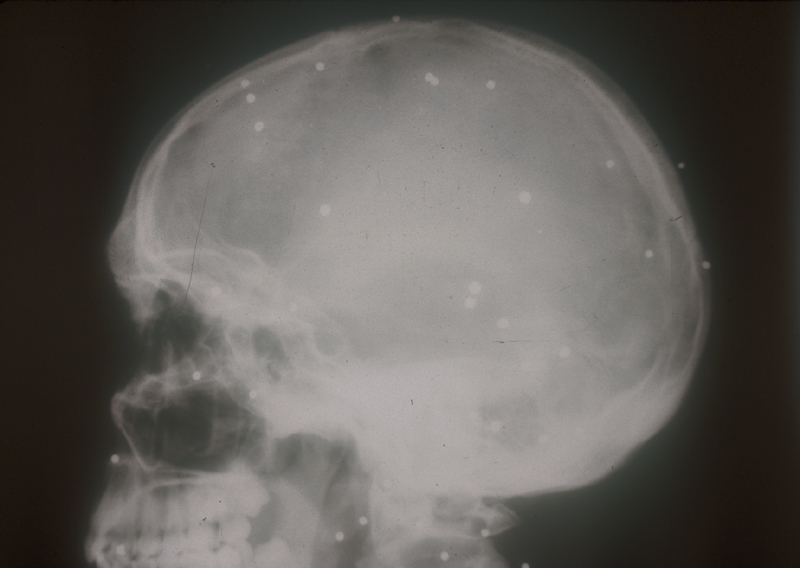

arma_fuego_cabeza2.JPG (229722 bytes)

Herida en cabeza

arma_fuego_cabeza.JPG (280287 bytes)